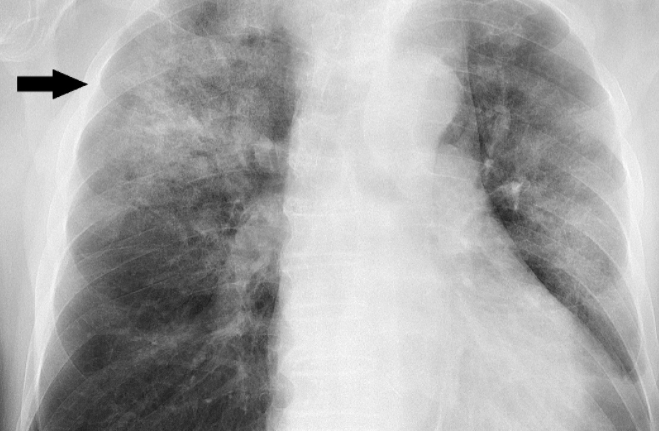

발생 부위는 폐이며 중증의 경우는 입원이 필요합니다. 전형적인 증상은 대부분은 38도 이상의 고열과 기침, 노란색이나 녹색 가래, 숨가쁨, 가슴통증 등이 있습니다. 특히 가래 색깔은 폐렴 구균감염증은 적갈색 즉 녹슨 색깔의 가래를 볼 수 있습니다.

폐렴 원인은 폐렴구균, 인플루엔자균 등의 세균과 라이노바이러스, 인플루엔자바이러스, RS바이러스, 파라인플루엔자바이러스, 코로나 바이러스 등이 있습니다.